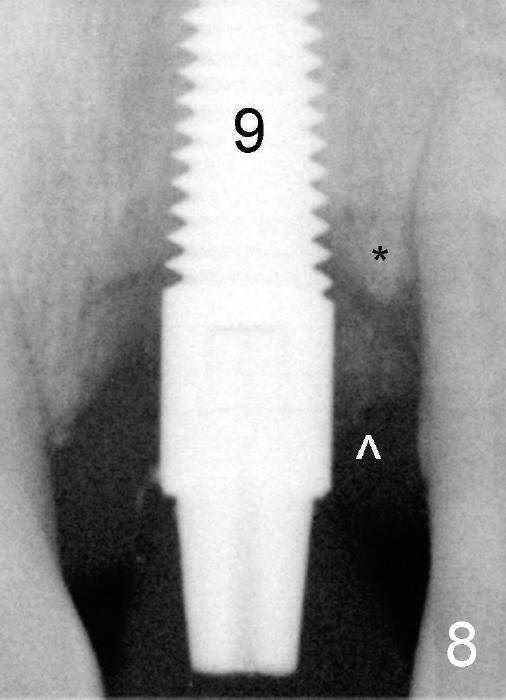

Fig.8: One and a half months postop. There is apparent separation between the crest bone (*) and bone graft (^).